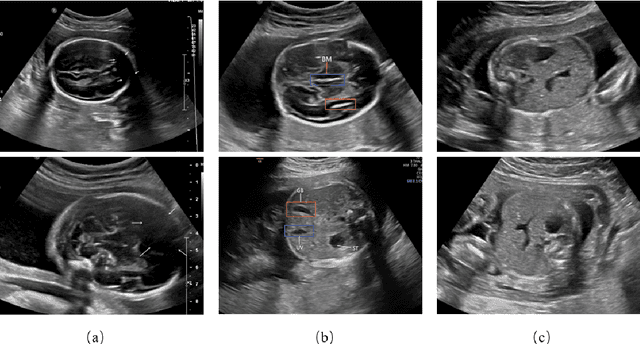

Abstract:The quality control of fetal sonographic (FS) images is essential for the correct biometric measurements and fetal anomaly diagnosis. However, quality control requires professional sonographers to perform and is often labor-intensive. To solve this problem, we propose an automatic image quality assessment scheme based on multi-task learning to assist in FS image quality control. An essential criterion for FS image quality control is that all the essential anatomical structures in the section should appear full and remarkable with a clear boundary. Therefore, our scheme aims to identify those essential anatomical structures to judge whether an FS image is the standard image, which is achieved by three convolutional neural networks. The Feature Extraction Network aims to extract deep level features of FS images. Based on the extracted features, the Class Prediction Network determines whether the structure meets the standard and Region Proposal Network identifies its position. The scheme has been applied to three types of fetal sections, which are the head, abdominal, and heart. The experimental results show that our method can make a quality assessment of an FS image within less a second. Also, our method achieves competitive performance in both the detection and classification compared with state-of-the-art methods.